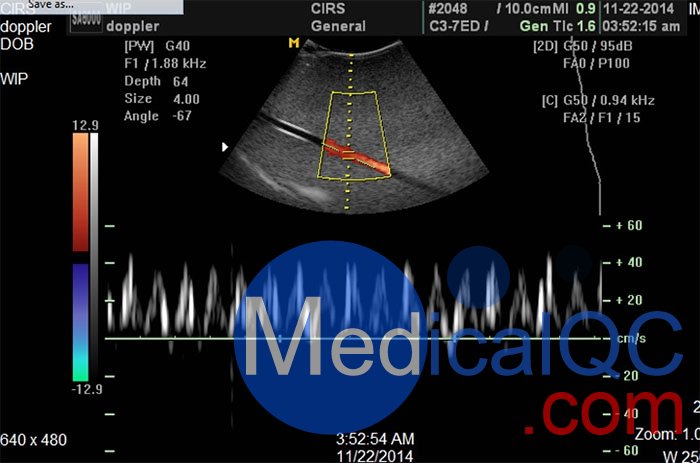

| CIRS 069多普勒超聲血流模擬器產品規格 | ||

| 組織等效體模 | ||

| 外形尺寸 | 20×12.5×27.5厘米 | |

| 管道 |

內部尺寸:3/16“ 外部尺寸:1/4” |

| 掃描表面 | Saran層壓膜:12.5 x 17.5厘米 | |

| 背景材料 |

Zerdine ® SOS:1540米/秒±10m / s的 衰減:0.7分貝/厘米兆赫 |